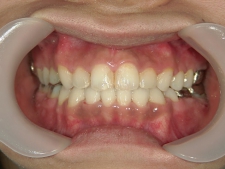

矯正歯科 治療後矯正歯科 全顎ワイヤー矯正 治療後矯正歯科(全顎ワイヤー矯正)治療後

30歳女性 浜松市北区在住

治療期間3年4ヶ月

主訴:前歯の歯並びが気になる。

矯正歯科 治療前 上顎を装置(QH)で拡大後ワイヤー矯正へ移行、右下5番左下4番 計2本抜歯叢生改善